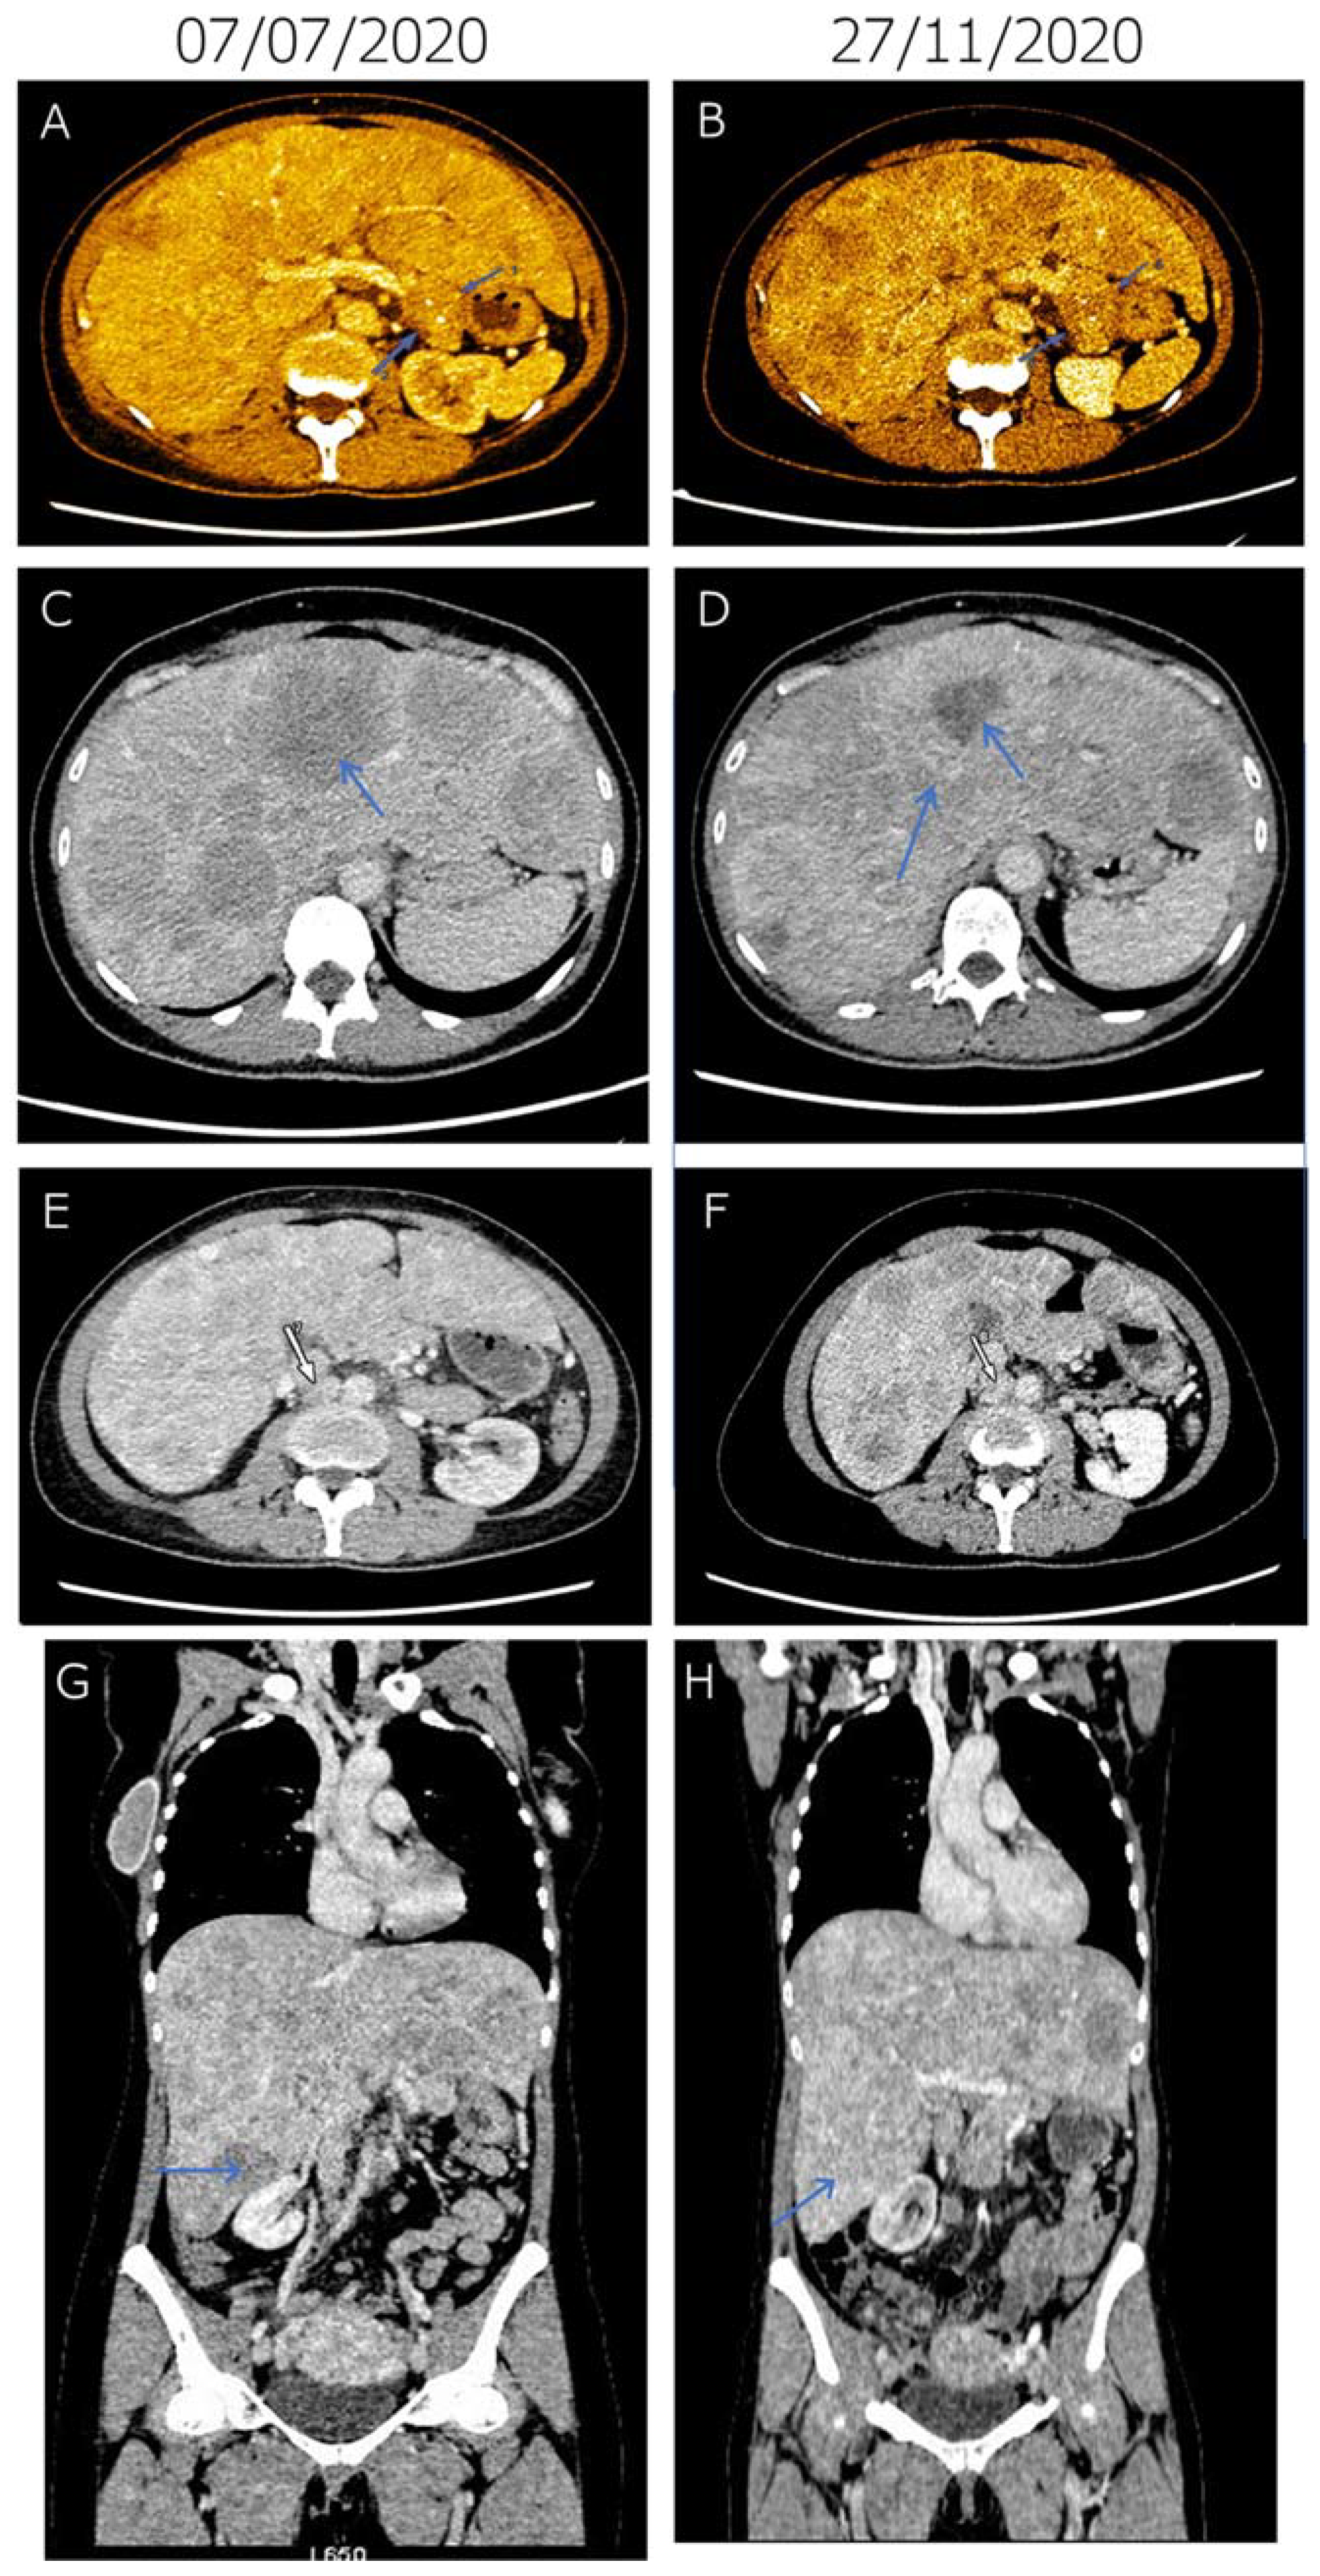

2. Case Report